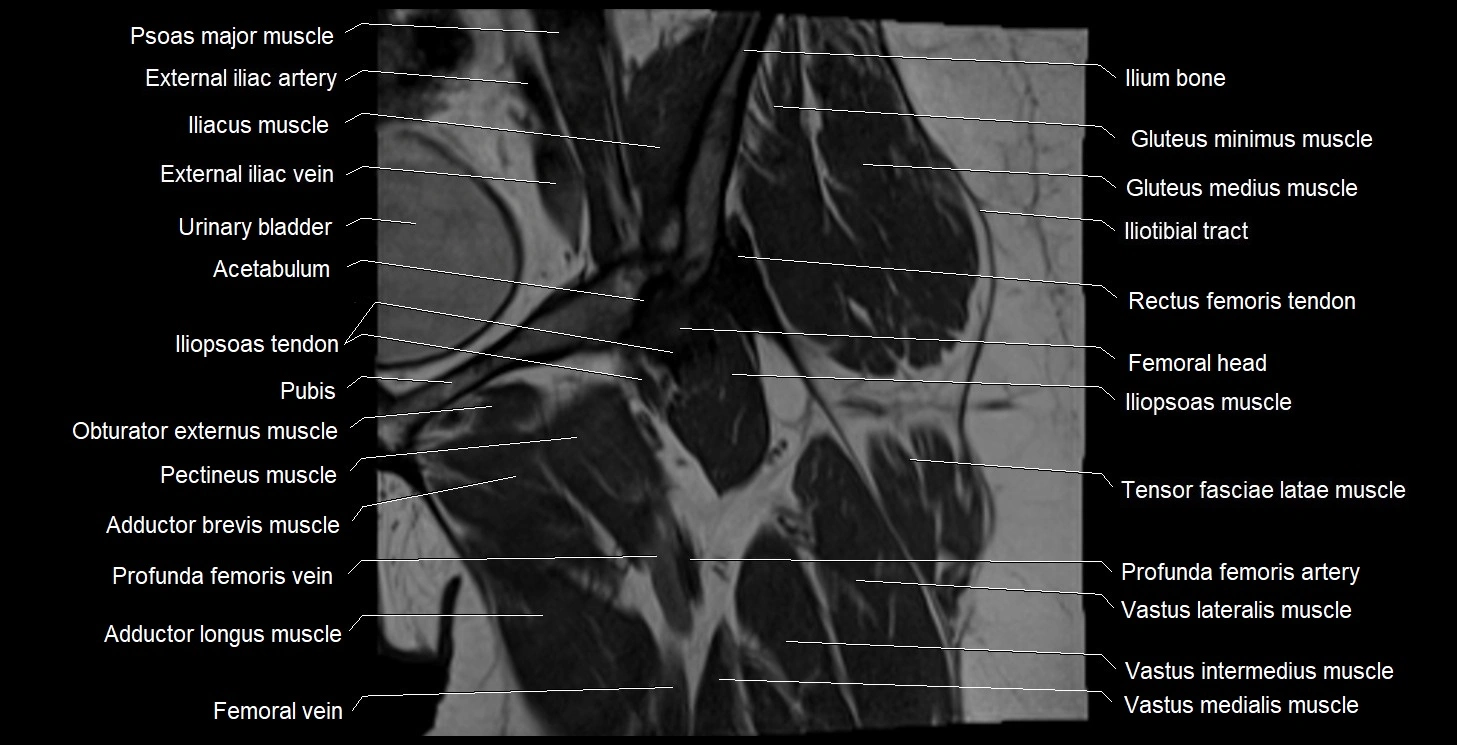

- Acetabulum

- Deep femoral vein (profunda femoris vein)

- External iliac artery

- External iliac vein

- Femoral vein

- Gluteus medius muscle

- Gluteus minimus muscle

- Iliopsoas muscle

- Iliopsoas tendon

- Iliotibial tract

- Ilium bone

- Obturator externus muscle

- Pectineus muscle

- Psoas major muscle

- Rectus femoris tendon (Proximal tendon of rectus femoris)

- Tensor fasciae latae muscle

- Urinary bladder

- Vastus intermedius muscle

- Vastus lateralis muscle

- Vastus medialis muscle